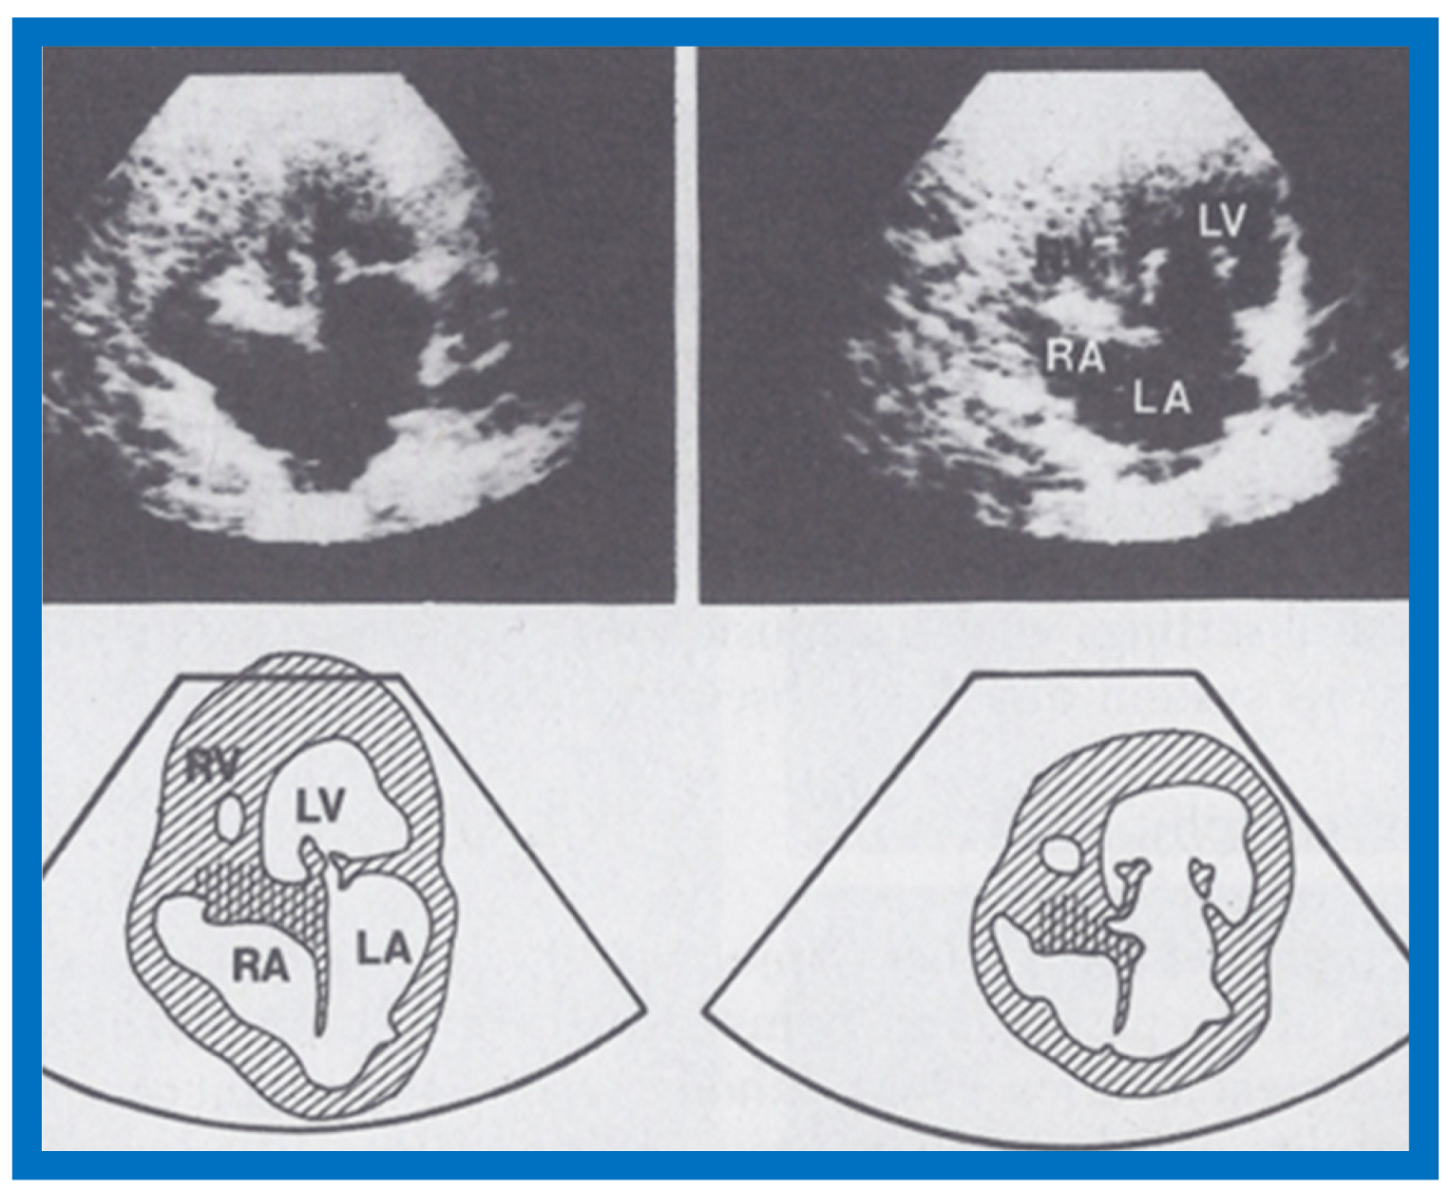

6. Echocardiographic Features of Tricuspid Atresia

The M-mode and two-dimensional echocardiographic features of tricuspid atresia were discussed in the author’s first book on tricuspid atresia, written in collaboration with his colleague, Dr Wesley Covitz at the Medical College of Georgia [7]. The two-dimensional (2D) echocardiographic pictures in 1982 were crude (Figure 14) [7]; however, they represented the state of the art echocardiography machines of that time.

Figure 14.

Selected video frames from apical four-chamber view of a two-dimensional (2-D) echocardiographic study demonstrating dense band of echoes between the right atrium (RA) and hypoplastic right ventricle (RV). Line drawings are shown beneath the 2D frames. Note that the mitral valve is closed in the left image while it is open in the right image. The atretic tricuspid valve echoes remain unchanged. LA, left atrium; LV, left ventricle. Reproduced from Covitz W., Rao P.S. [7].